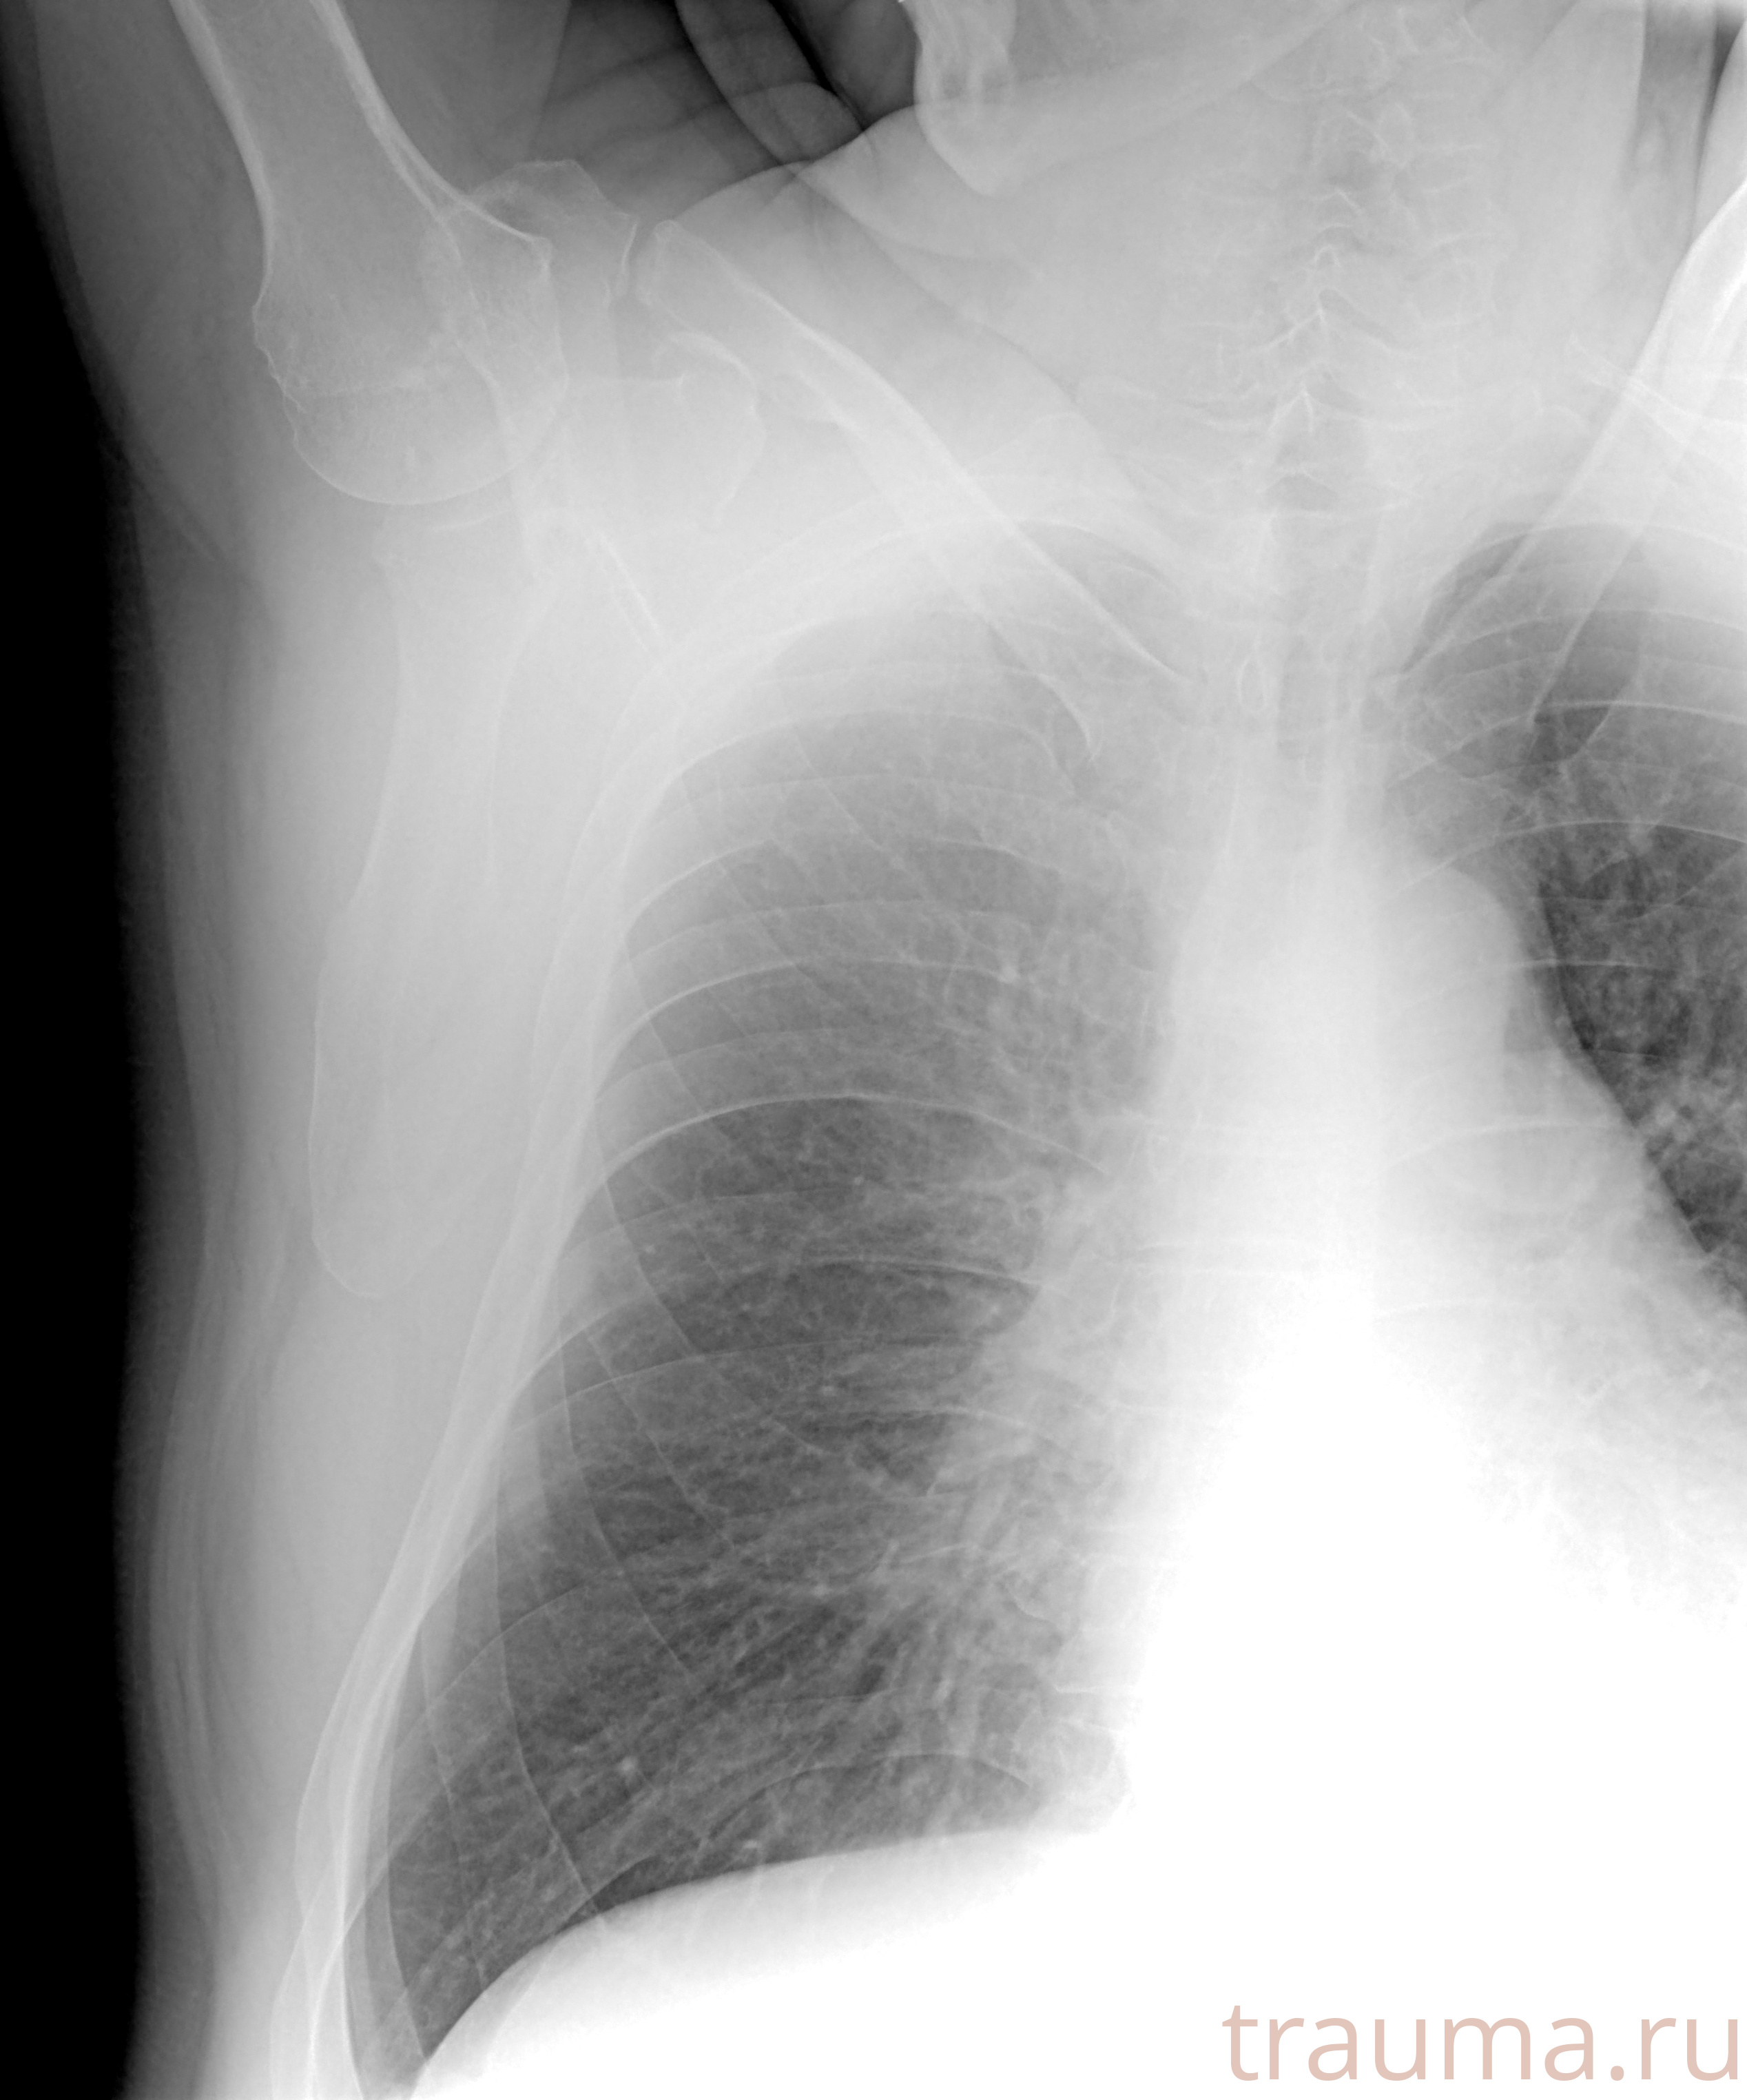

Рентгенограммы

Рентген на дому: по вашему адресу приезжает врач-рентгенолог, травматолог-ортопед с мобильным рентгеновским аппаратом, проводит диагностику травмы или заболевания, делает необходимые рентгенограммы, дает рекомендации по дальнейшему лечению. Получить качественные снимки в домашних условиях возможно благодаря уникальной методике, разработанной МосРентген Центром для института  Склифосовского

при переломе шейки бедра и пневмонии от компании МосРентген Центр - партнера Института имени Склифосовского